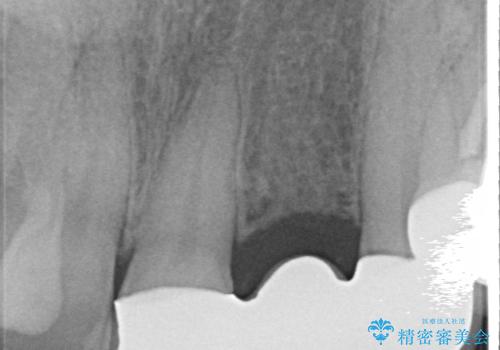

- 左上2番目の歯がグラグラするので診て欲しいといらっしゃった方の症例です。

左上2番目の歯は歯根が破折してため抜歯し、左上123のブリッジによる欠損補綴を行いました。

左上4、5番目の歯は根尖病変を認めたため再根管治療を行い、オールセラミッククラウンによる補綴を行いました。

なお左上4に関しては縁下歯質を改善するため、歯冠挺出を行っております。